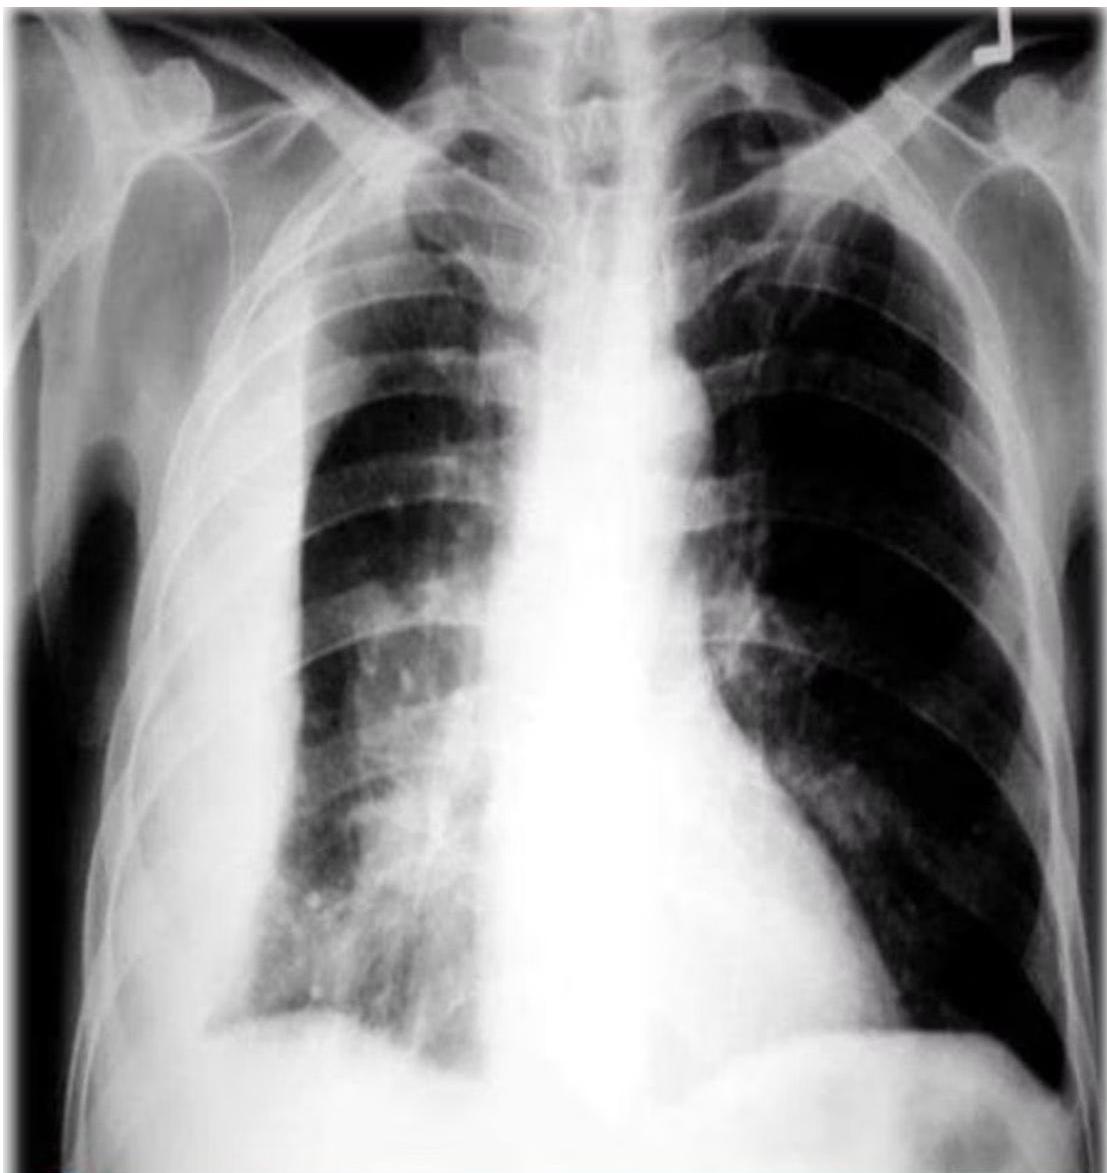

(b) Chest X-ray of pulmonary TB. There is marked left hilar lymphadenopathy.

Pediatric chest x-ray showing hilar lymphadenopathy tuberculosis.

Chest x-ray showing diffuse bilateral opacities.

- Hilar/Mediastinal Adenopathy: Most common abnormal finding; often the only visible abnormality in early disease.

Radiography is cornerstone for diagnosis in children due to clinically silent presentations. All lobar segments equally at risk for initial infection. • 25% of cases involve two or more lobes • Hilar lymphadenopathy inevitably present • Partial bronchial obstruction causes air trapping • Progressive destruction leads to cavitation

Diagnostic Imaging Findings Normal Chest X-ray Children with latent TB infection (LTBI) usually have normal-appearing chest radiographs. An isolated calcified lesion with positive TST can be treated as LTBI. Hilar/Mediastinal Adenopathy The most common abnormal radiographic finding in pediatric pulmonary TB. May be the only visible abnormality in early disease. Other Findings Infiltrates, atelectasis, pleural effusions, cavity lesions, or miliary disease pattern may be present in advanced cases.